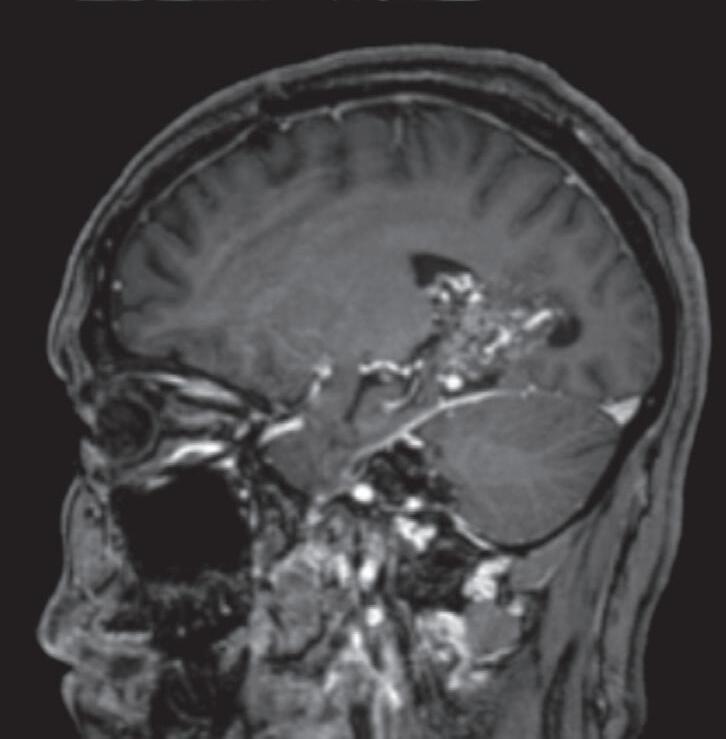

Fig. 1-8. (a-c) RNM T1 com contraste, cortes sagital (a), coronal (b) e axial (c) demonstrando MAV não rota com nidus localizado no lobo occipital à esquerda (setas longas). (d) Arteriografia digital cerebral com injeção de contraste via carótida direita (AP) mostrando a contribuição da carótida direita na irrigação da MAV contralateral. (e,f) Com injeção de contraste via carótida esquerda, em Perfil e AP respectivamente, observa-se nidus compacto nutrido por ramos da artéria cerebral média à esquerda e a veia de drenagem precoce se dirigindo para o seio sagital superior. Projeções em AP (g) e em perfil (h) demonstrando a contribuição do sistema vertebrobasilar por meio de ramos distais da artéria cerebral posterior à esquerda e drenagem para os seios sagital superior e sigmoide à esquerda (setas curtas).